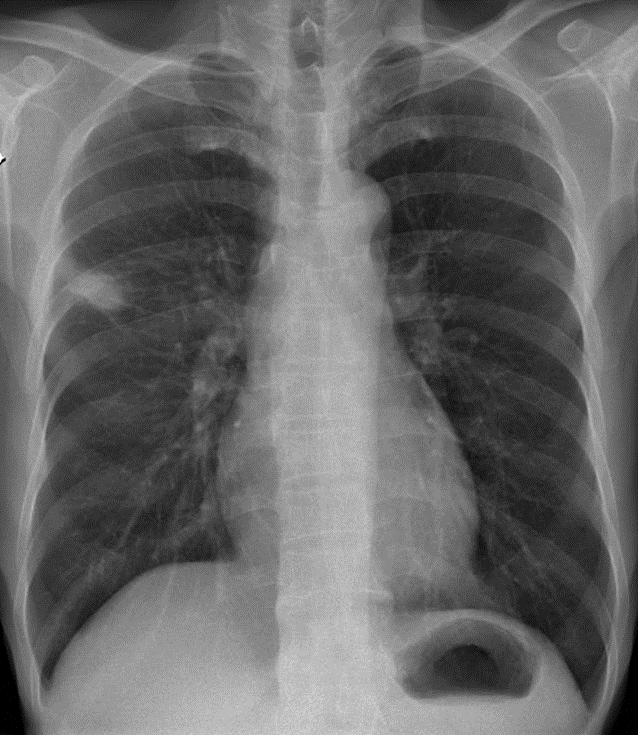

1-U thùy trên phổi (P)